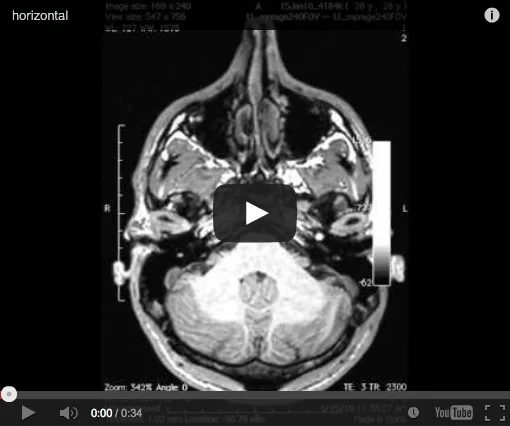

It’s one thing to study the human brain, and another to see your own in 3D. Here are my optic nerves, ventricles, cerebellum, spinal cord—wow. These images came from a memory study in a 3T research MRI scanner.